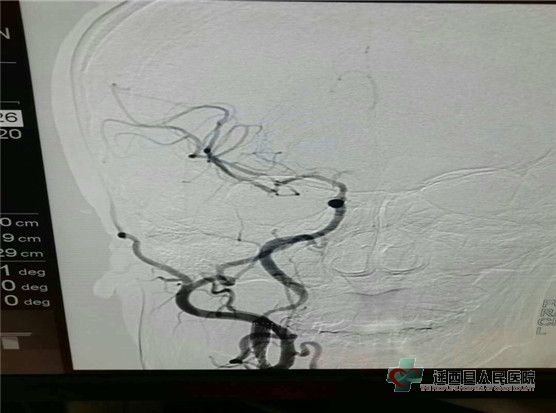

患者推入介入室,行全脑血管造影术

造影结果显示:右侧颈内动脉起始部重度狭窄

首先上导丝 导管通过颈内动起始部,再次造影显示右侧大脑中动脉M1段闭塞

考虑串联病变,右侧颈内动脉起始部慢性狭窄,右侧大脑中动脉M1段急性闭塞,赵士军主任决定给予右侧大脑中动脉机械取栓,右侧颈内动脉起始部支架置入,上导丝、导管、取栓支架。